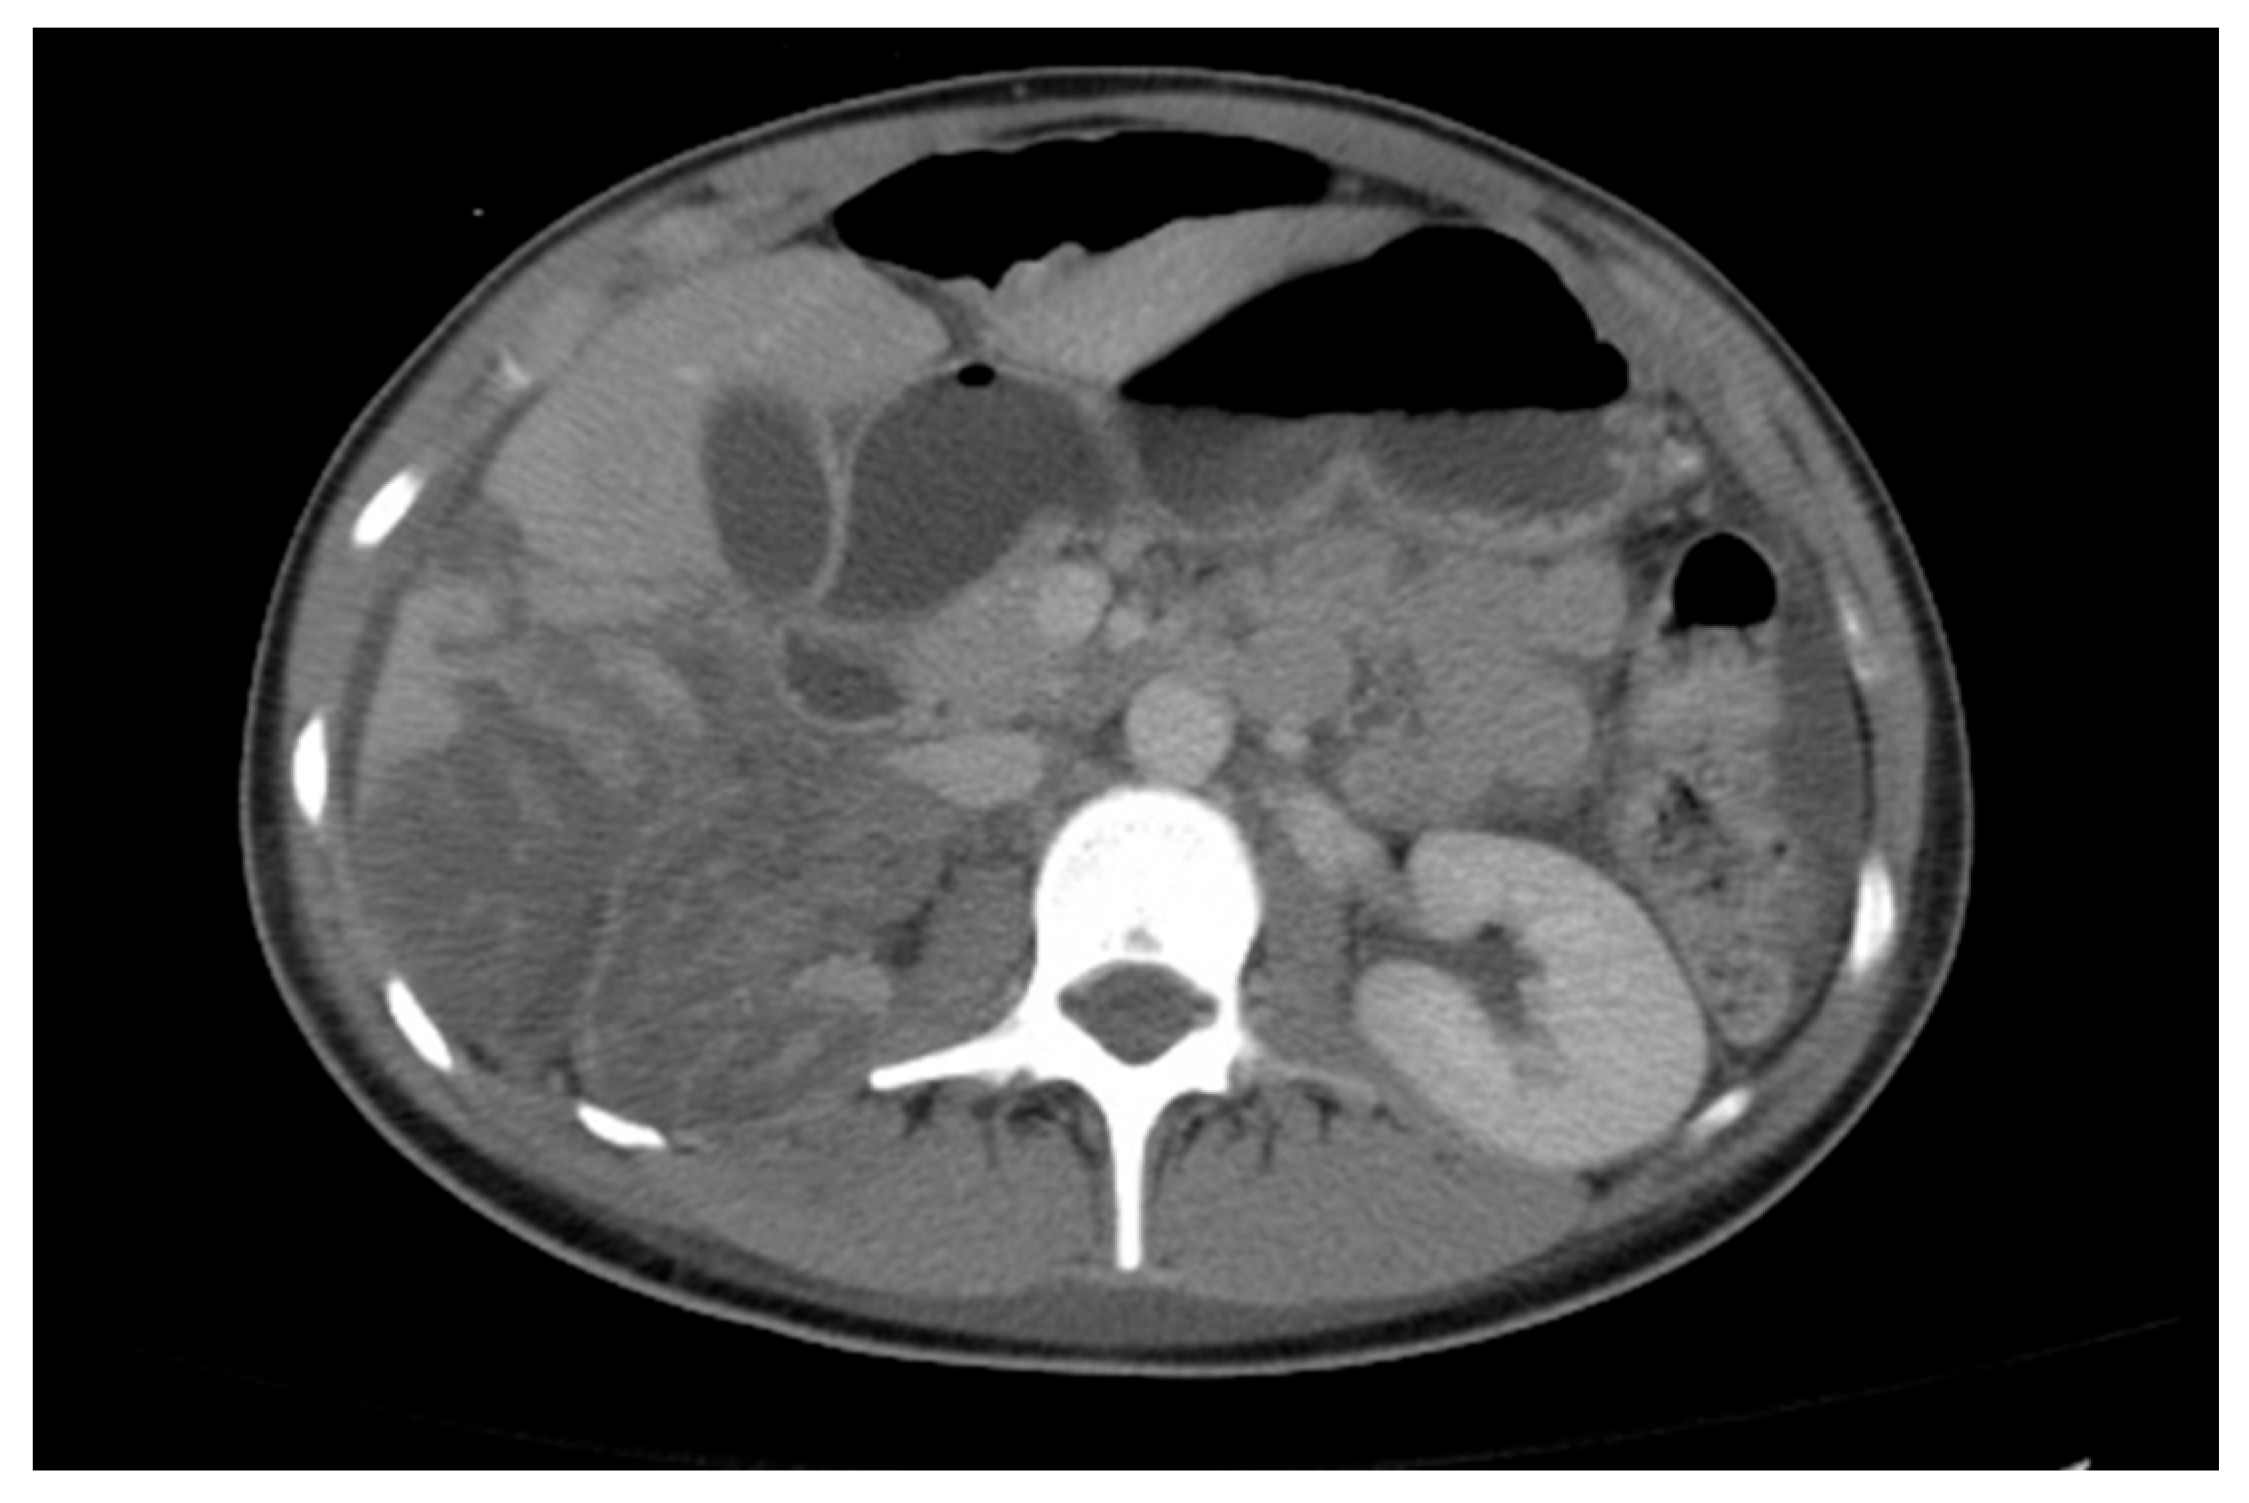

22.3. Nutcracker Syndrome